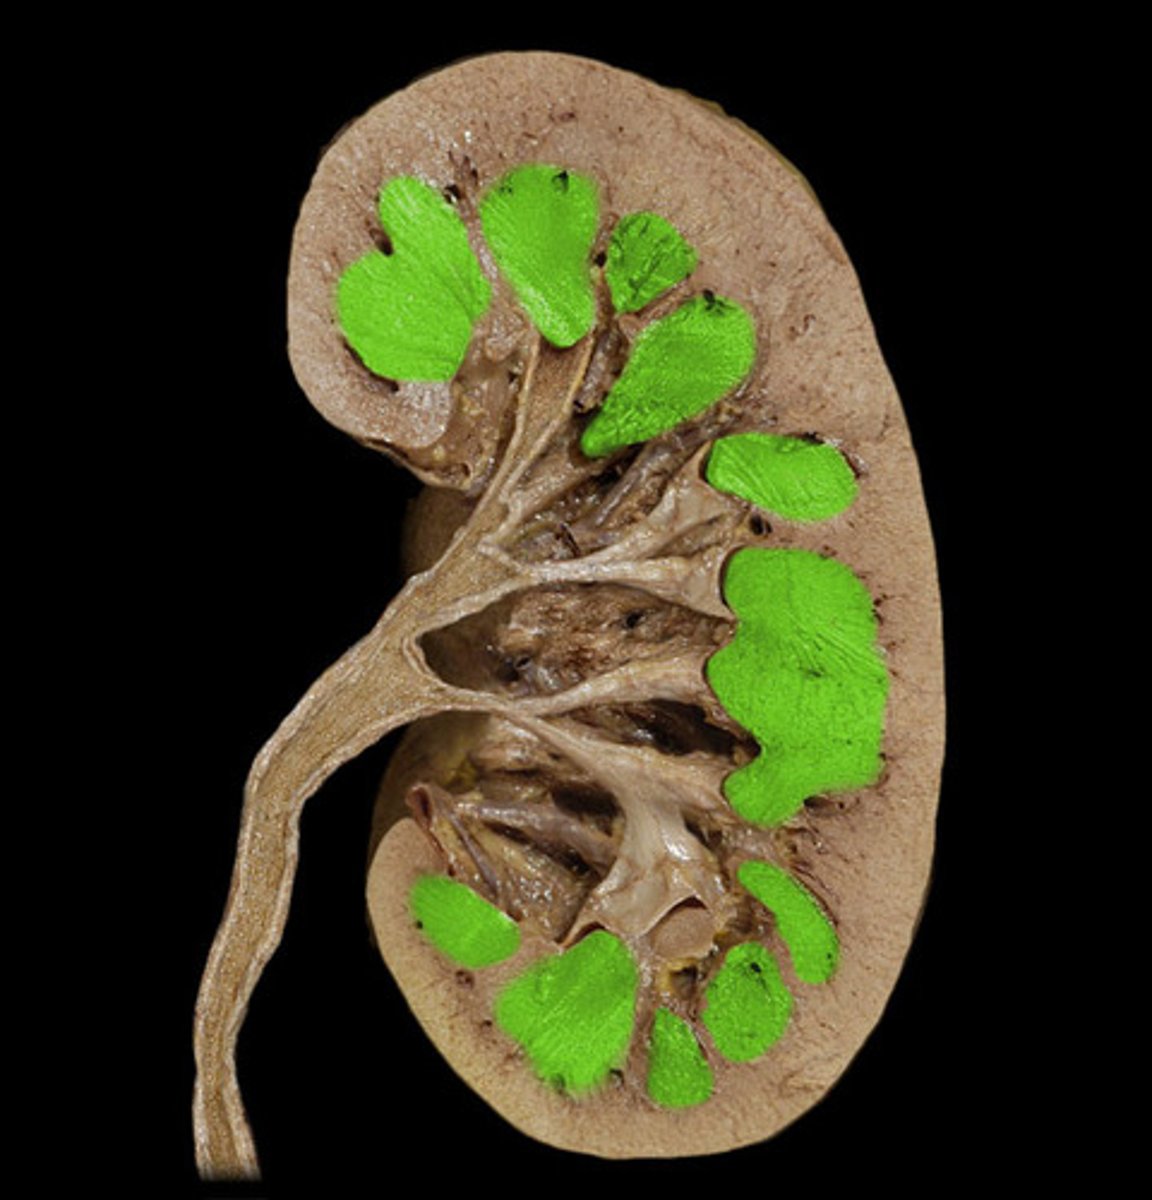

What is this?

Renal pyramids

Renal papillae